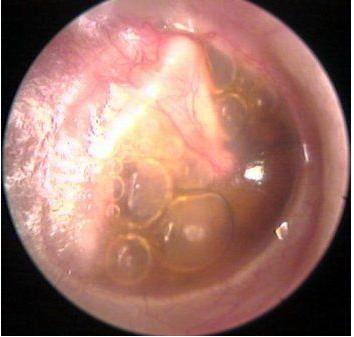

西安新城中大耳鼻喉医院医生表示:用耳内窥镜检查病人的耳部,会发现鼓膜内陷,鼓膜呈淡黄或橙红色,有时透过鼓膜可见气泡。

上图就是一例分泌性中耳炎的鼓膜表现,透过鼓膜可见内有气泡,说明鼓室内有积液